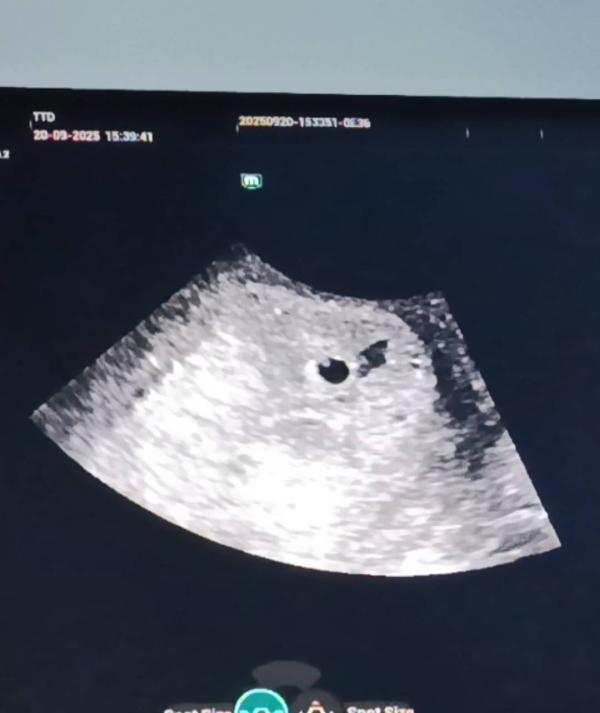

Я сходила на УЗИ ❤️🥰🙏

Плодное яйцо в матке 4мм

ЖМ почему-то замеров нет,но он есть)

Теперь на повторное УЗИ через 7-10 дней уже слушать сердцебиение ❤️❤️❤️